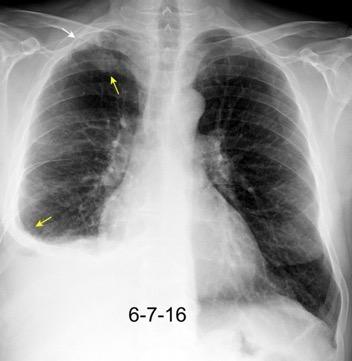

Nefrectomia derecha en 1996 por adenocarcinoma renal. Reseccion de metastasis pulmonar en LSI de carcinoma renal. Sospecha de nueva metástasis.

Granuloma de cuerpo extrano por hilo de sutura en situación cisural

Madan Ret al. Intrathoracic gossypiboma. AJR 2007/Anderson JM et al. FOREIGN BODY REACTION TO BIOMATERIALS. Semin Inmunol 2008/Okazaki M et al. Two cases of granuloma mimicking local recurrence after pulmonary segmentectomy. Journal of Cardiothoracic Surgery. 2020